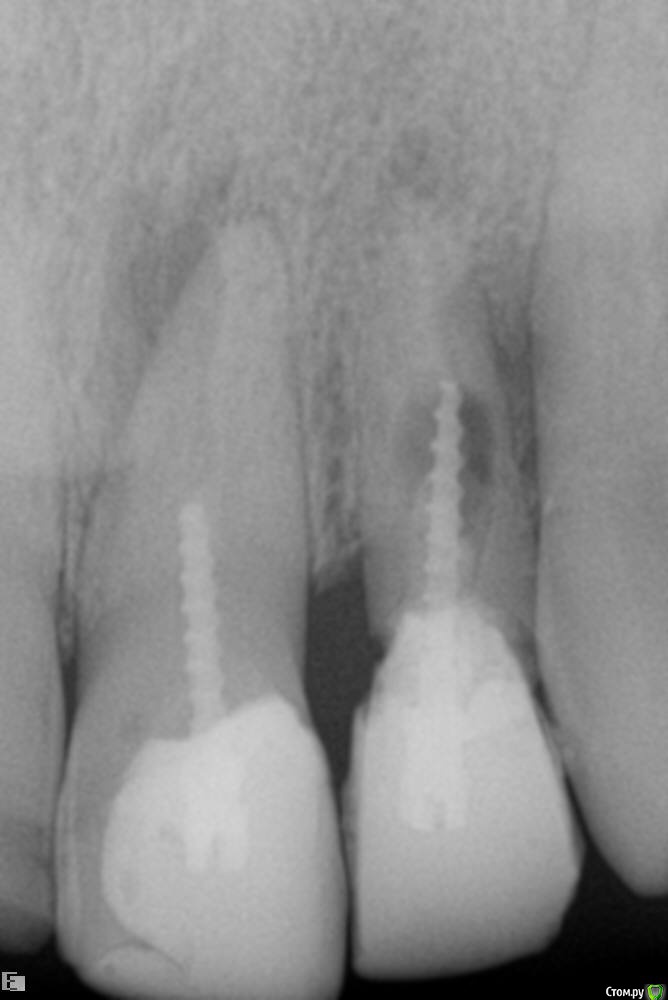

Westika Опубликовано 20 февраля, 2020 Поделиться Опубликовано 20 февраля, 2020 7 февраля поставили старый штифт повторно на цемент. На следующий день зуб и соседние стали ныть. Сделали снимок 8 числа - рекомендация удаление штифта с корнем. 9 февраля опухла щека + температура. 10 числа нашла своего стоматолога терапевта-выдавил мне гной. Была на консультация у нескольких стоматологов - все говорят удалять. На сейчас гной при надавливании из десны выходит. Десна припухшая. Есть варианты лечения? Ссылка на комментарий